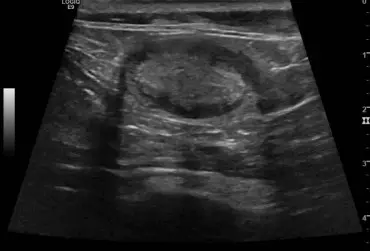

Zespół gruczolakoraka torbielowatego nerek i guzków włóknistych skóry u owczarka niemieckiego – opis przypadku

U 8-letniego niekastrowanego owczarka niemieckiego wykryto obecność kilku guzków skórnych widocznych na kończynach i na nosie. Badanie cytologiczne nie było jednoznaczne. W badaniu histopatologicznym jednego z usuniętych guzków stwierdzono obecność masy kolagenowej z niewielką ilością komórek zajętych głębokim, ropnym zapaleniem skóry. Po roku wykonano badanie ultrasonograficzne układu moczowego z powodu krwiomoczu i pogorszenia się stanu ogólnego psa. Wykryto liczne torbiele w obu nerkach o nietypowej strukturze. Na podstawie wyników badań postawiono rozpoznanie zespołu gruczolakoraka torbielowatego nerek i guzków włóknistych skóry (ang. renal cystadenocarcinoma and nodular dermatofibrosis – RNCD).